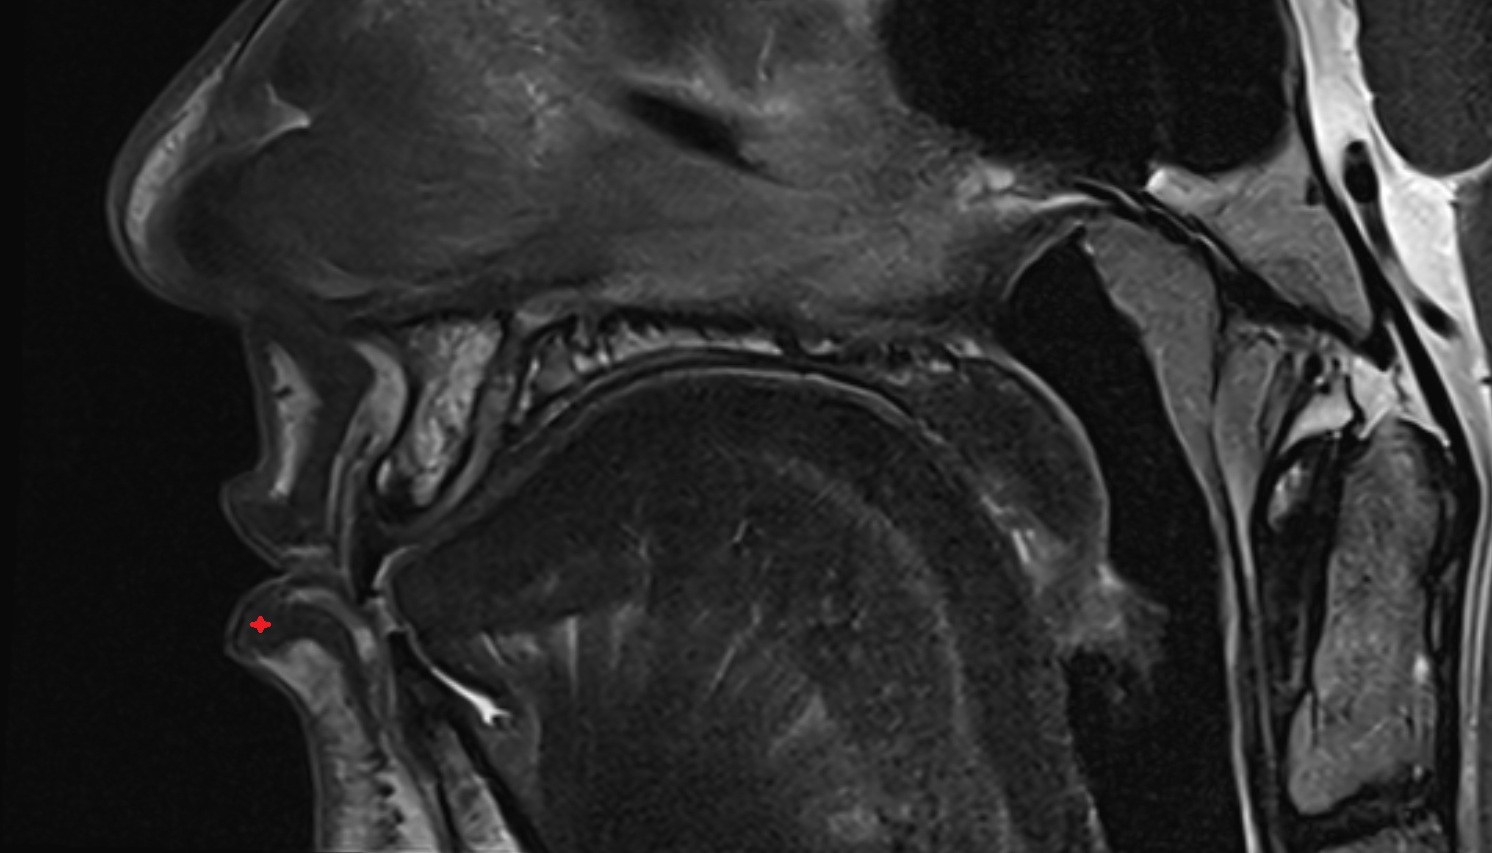

- Temporomandibular joint

- Articular disc of temporomandibular joint

- Articular eminence

- Mandibular condyle

- Mandibular fossa

- Superior head of lateral pterygoid muscle

- Inferior head of lateral pterygoid muscle